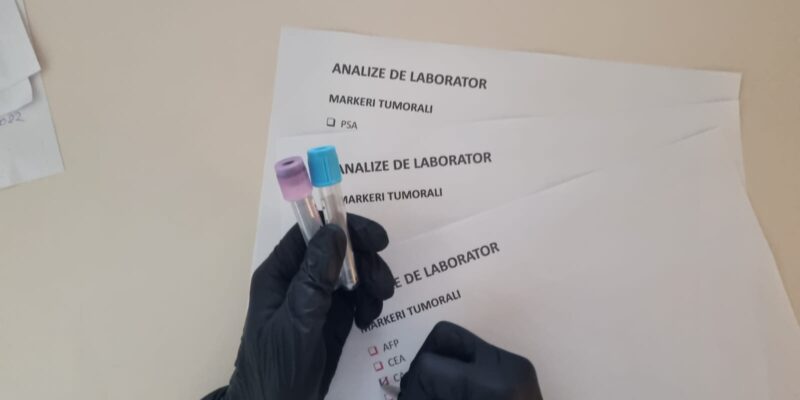

MARKERII TUMORALI (partea întâi)

Markerii tumorali sunt componente produse de obicei de celulele tumorilor maligne, inclusiv cele situate la nivelul esofagului, stomacului, intestinului sau rectului. În general pentru toate cancerele acești markeri pot fi depistați direct în țesutul tumoral sau pot fi prezenți în...

MARKERII TUMORALI UTILIZAȚI ÎN CANCERUL COLORECTAL (partea a doua)

În cancerul de colon sau în cel rectal există anumiți markeri tumorali care sunt mai frecvent crescuți în cazul prezenței acestor patologii. CEA sau antigenul carcinoembrionar este o glicoproteină care este sintetizată la nivelul pancreasului și tractului gastrointestinal însă, în...